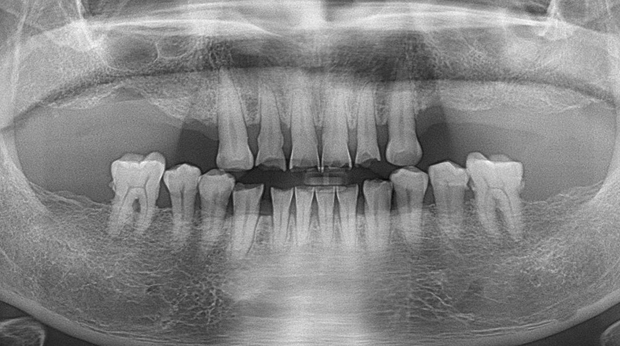

매복 사랑니 발치

임플란트와 사랑니 발치는 외과적 시술로 잇몸을 절개하는 외과적 시술은

짧으면 짧을 수록 시술 후 붓기와 통증이 최소화됩니다.

치과의사 경력 14년차 구강외과 전문의가 빠르고 안전하게, 아프지 않게 수술해 드립니다.